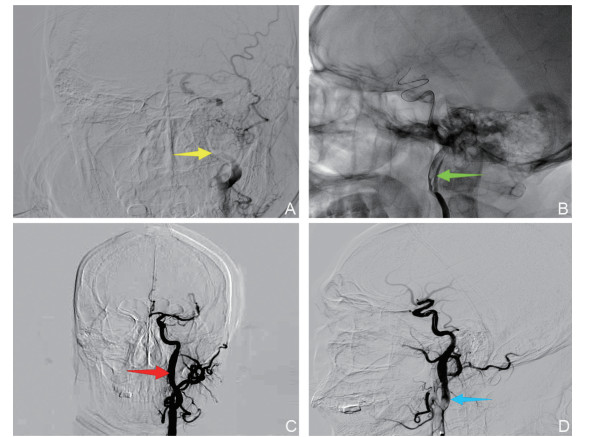

急性缺血性脑卒中在院内发生的风险因素及预测价值分析

迪丽达热·艾尔肯, 西合热扎提·阿布力米提, 田睿思

2025, 23(10): 1643-1646. doi: 10.16766/j.cnki.issn.1674-4152.004195

4 0

摘要:

目的  鉴于院内发生的急性缺血性脑卒中(IHS)因患者基础疾病复杂、治疗背景特殊,常导致诊断延迟和预后不良,本研究旨在识别IHS发生的独立危险因素,并评估其预测价值,为临床早期识别和干预提供依据。  方法  回顾性选取2015年1月—2020年1月于新疆医科大学第二附属医院神经内科住院发生急性缺血性脑卒中的85例患者作为院内组,选取同期因急性缺血性脑卒中住院的170例患者作为对照组(院外组)。分析2组患者的一般资料,采用logistic回归分析研究影响院内急性缺血性脑卒中发生的因素;采用受试者工作特征曲线(ROC)分析各因素对院内急性缺血性脑卒中的预测价值。  结果  心功能不全(OR=5.202, 95% CI:1.436~18.849)、发病时mRS评分≥3分(OR=3.602, 95% CI:1.809~7.175)、围手术期(OR=4.085, 95% CI:1. 391~11. 997)、前循环+后循环梗死(OR=1.959, 95% CI:1.270~3.022)、心源性栓塞型(OR=2.312, 95% CI:1.257~4.253)均为院内急性缺血性卒中发生的独立危险因素(P<0.05)。心功能不全、发病时高mRS评分、围手术期、前循环+后循环梗死、心源性栓塞型预测IHS的AUC分别为0.705、0.720、0.736、0.751、0.782,5项指标联合预测的AUC为0.913。  结论  心功能不全、发病时高mRS评分、围手术期、前循环+后循环梗死及心源性栓塞型梗死是影响IHS发生的独立危险因素,并对IHS的发生具有一定的预测价值。